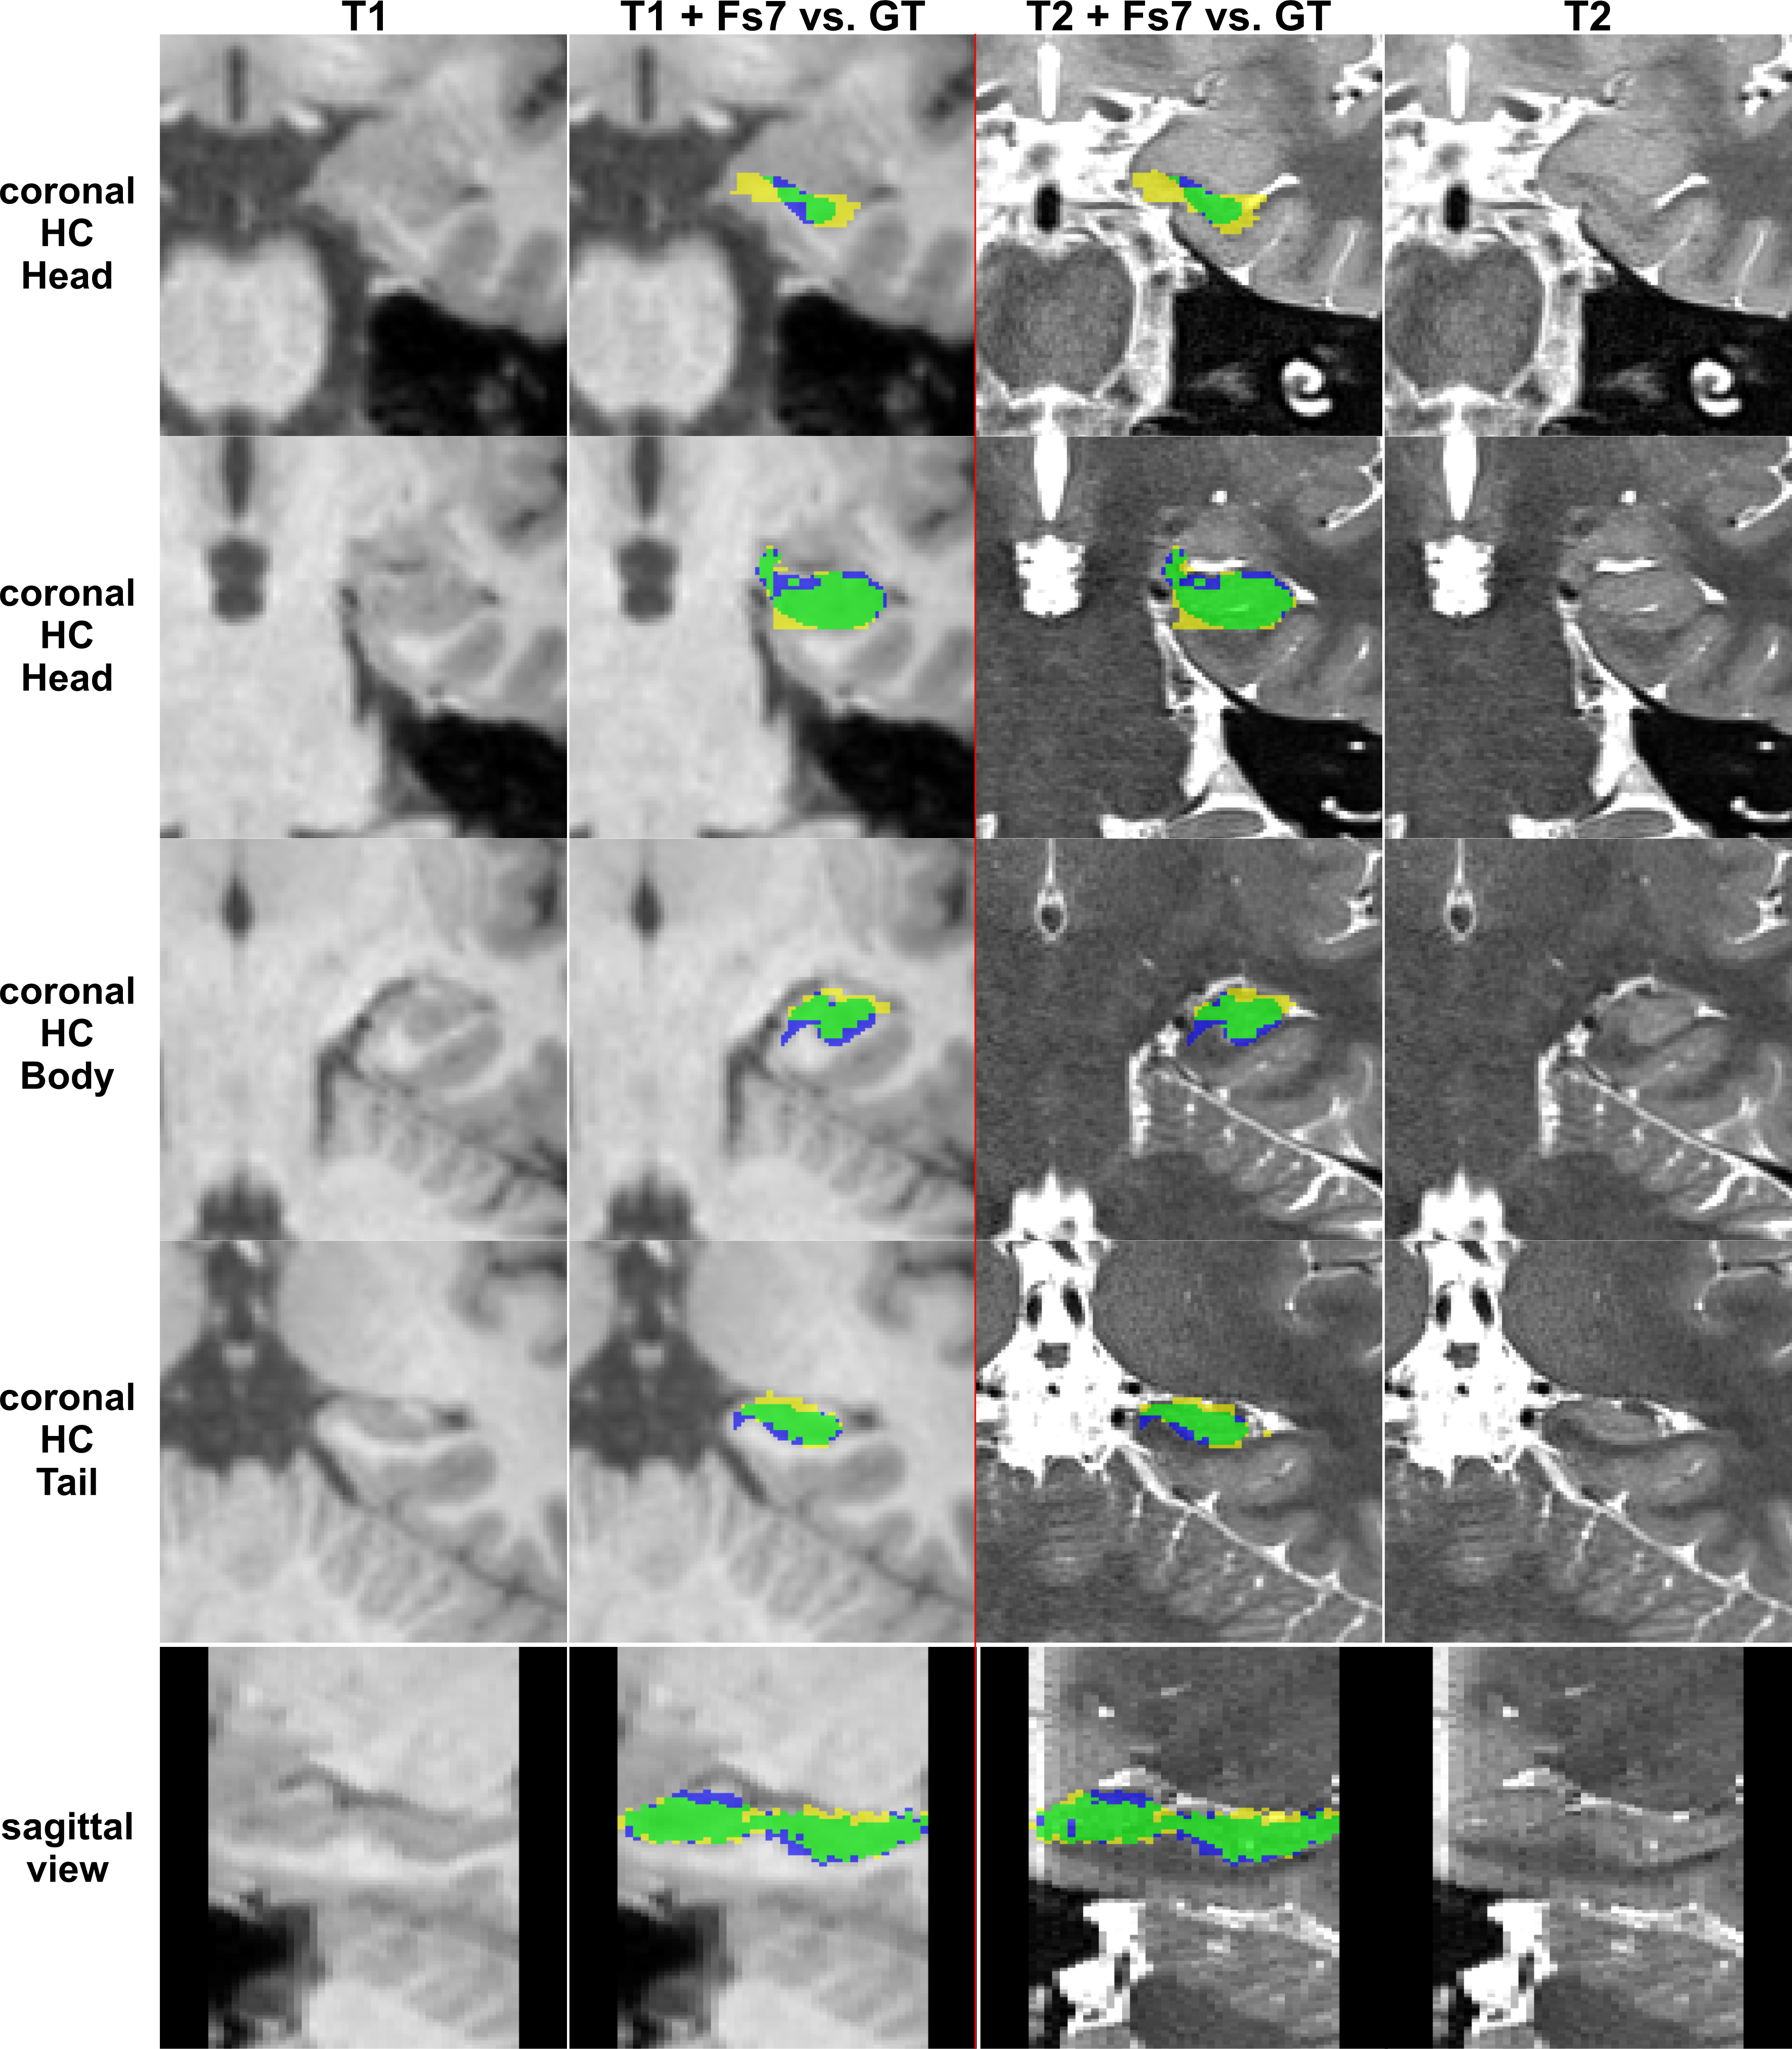

Training with our GT-labels yields a DSC of 86.7±0.2% for T1 images and 92.1±0.1% for T2 images (see Figure 5).

Figure 5: CNN-based segmentation pipeline results of the same subject. Left two columns show the CNN-mask vs. the GT-mask if trained on T1 input patches. Right two columns show the CNN-mask vs. the GT-mask if trained on T2 input patches. Legend: green = True Positives, yellow = False Positives, blue = False Negatives; CNN-masks = yellow+green, manual GT = green+blue.